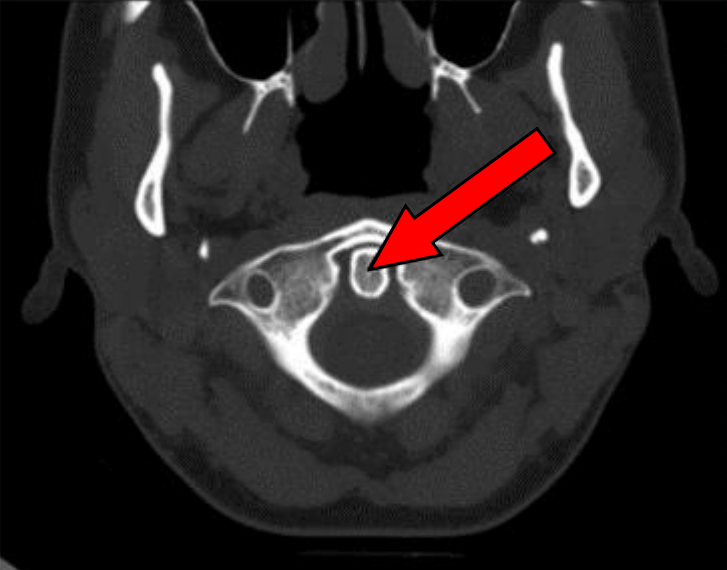

Na przekroju poprzecznym TK kręgosłupa szyjnego strzałką wskazano

A. otwór kręgu szczytowego.

B. guzek tylny kręgu szczytowego.

C. ząb kręgu obrotowego.

D. rdzeń kręgowy.